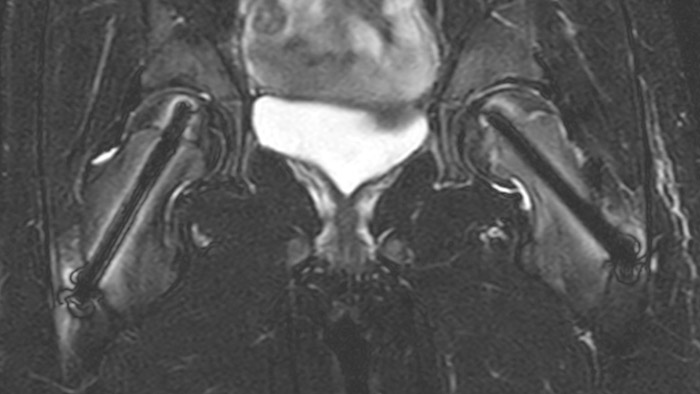

Perthes disease in left hip The affected area on the upper circumference of the left hip shows contrast uptake in the dynamic scan. The radial scan nicely depicts the hip area, despite the dark shape in the center that is inherent to the radial way of scanning.